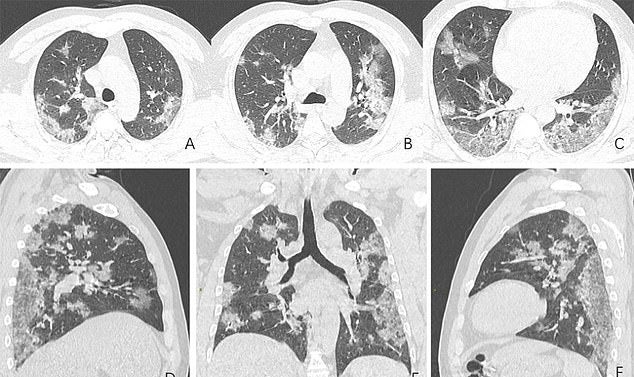

Röntgenbilder und CT-Aufnahmen, darunter die eines 44-jährigen Chinesen, der am Coronavirus gestorben ist, zeigen, wie die Krankheit die Lunge der Opfer verwüstet. Auf den Scans sind weiße Flecken zu sehen, die sich in den unteren Ecken der Lunge befinden. Radiologen bezeichnen das als Opazität des Grundglases - die teilweise Füllung von Lufträumen.

Die von der Radiological Society of North America veröffentlichten Scans zeigen, wie die Flüssigkeit in den Lungenräumen des Mannes im Laufe der Zeit anwuchs.

Bild A bis Bild F

Der Mann wurde am 25. Dezember 2019 ins Krankenhaus eingeliefert, nachdem er fast zwei Wochen lang an Fieber und Husten gelitten hatte. Die Ärzte diagnostizierten bei dem Mann eine Lungenentzündung und ein akutes Atemnotsyndrom. Obwohl er von Ärzten behandelt wurde, starb der 44-Jährige eine Woche später.